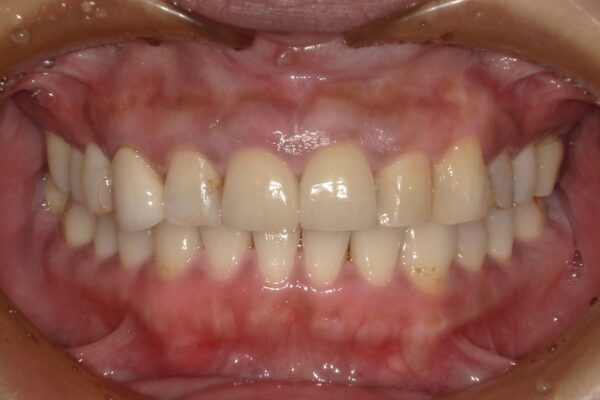

Images